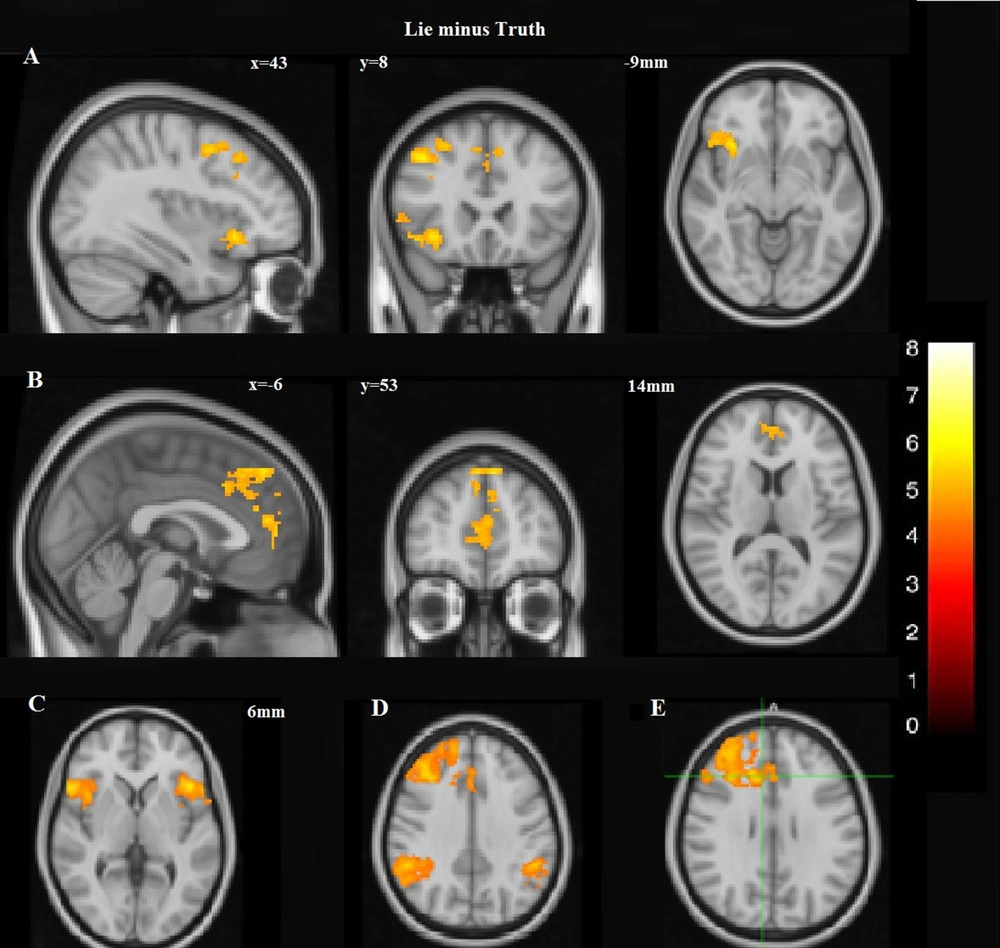

IMAGE 3

fMRI statistical maps from a study on brain activity during a monetary deception or truth task. Basically shows distributed activations when people lie or when cognitive control is recruited.

This illustrates that speech content and intent map to measurable differences in brain activation.